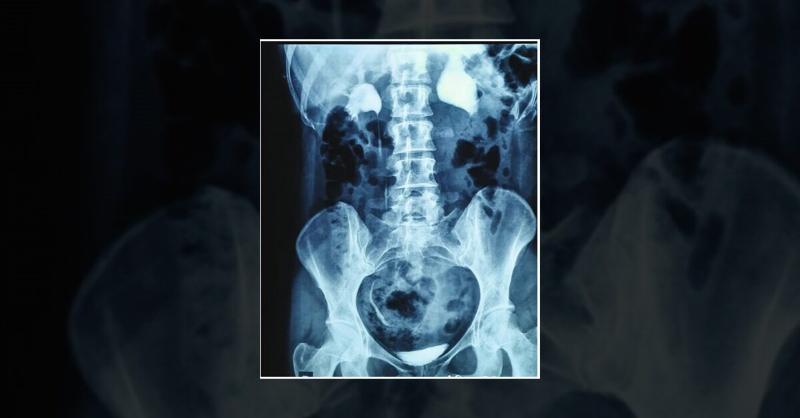

A 32-year-old woman with a history of left mild hydronephrosis, non-specific intermittent left flank pain, and equivocal DRG result was on observation. Despite 7 years of surveillance and ruling out vesicoureteral reflux, her symptoms worsened during the last 6 months with significant changes in her imaging findings. The patient did not report any

Ureteropelvic Junction Obstruction and Declining Kidney Function in an Adult Woman